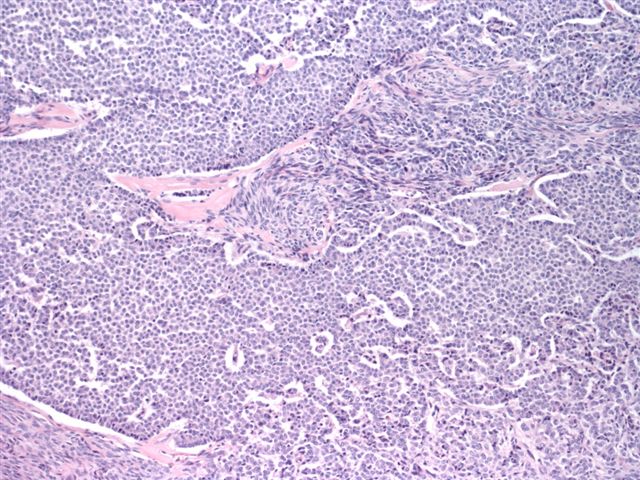

Frozen section description

- May be mistaken for endometrioid adenocarcinoma on frozen section

- Characteristic nuclear features can be helpful in diagnosis

- Small, bland, cuboidal to polygonal cells with scant cytoplasm and pale, uniform angulated and usually grooved nuclei (coffee bean)

- Various patterns, including diffuse (the most common), trabecular and corded, insular, microfollicular (resembling Call-Exner bodies of the Graafian follicles: small follicle-like structures filled with eosinophilic material) and macrofollicular (the least common)

- Usually a mixed growth pattern is seen

Contributed by Shabnam Zarei, M.D. and Sharon Bihlmeyer, M.D.

AFIP images

A 59 year old woman underwent abdominal hysterectomy and salpingo-oophorectomy for ovarian torsion and endometrial atypical hyperplasia. You receive a 10 cm hemorrhagic cystic ovarian mass for intraoperative consultation. Frozen section is shown above. What is the most common mutation identified in this ovarian tumor?